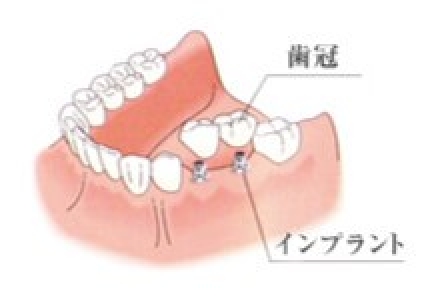

かみ合わせの回復について